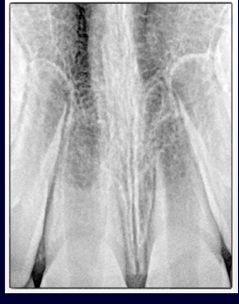

horizontal root fractures

-the more apical the fracture, the better the prognosis

-more apical means being more walled-off from the oral environment

-apical segment: blood supply maintained, never a problem

-coronal segment at risk: mobility, splint required for 4 weeks, RCT not needed (just observe)

-when coronal pulp necroses, see if you can reposition the segment and splint, or can do RCT on the coronal segment only

-if apical segment starts trouble, just do apicoectomy to treat